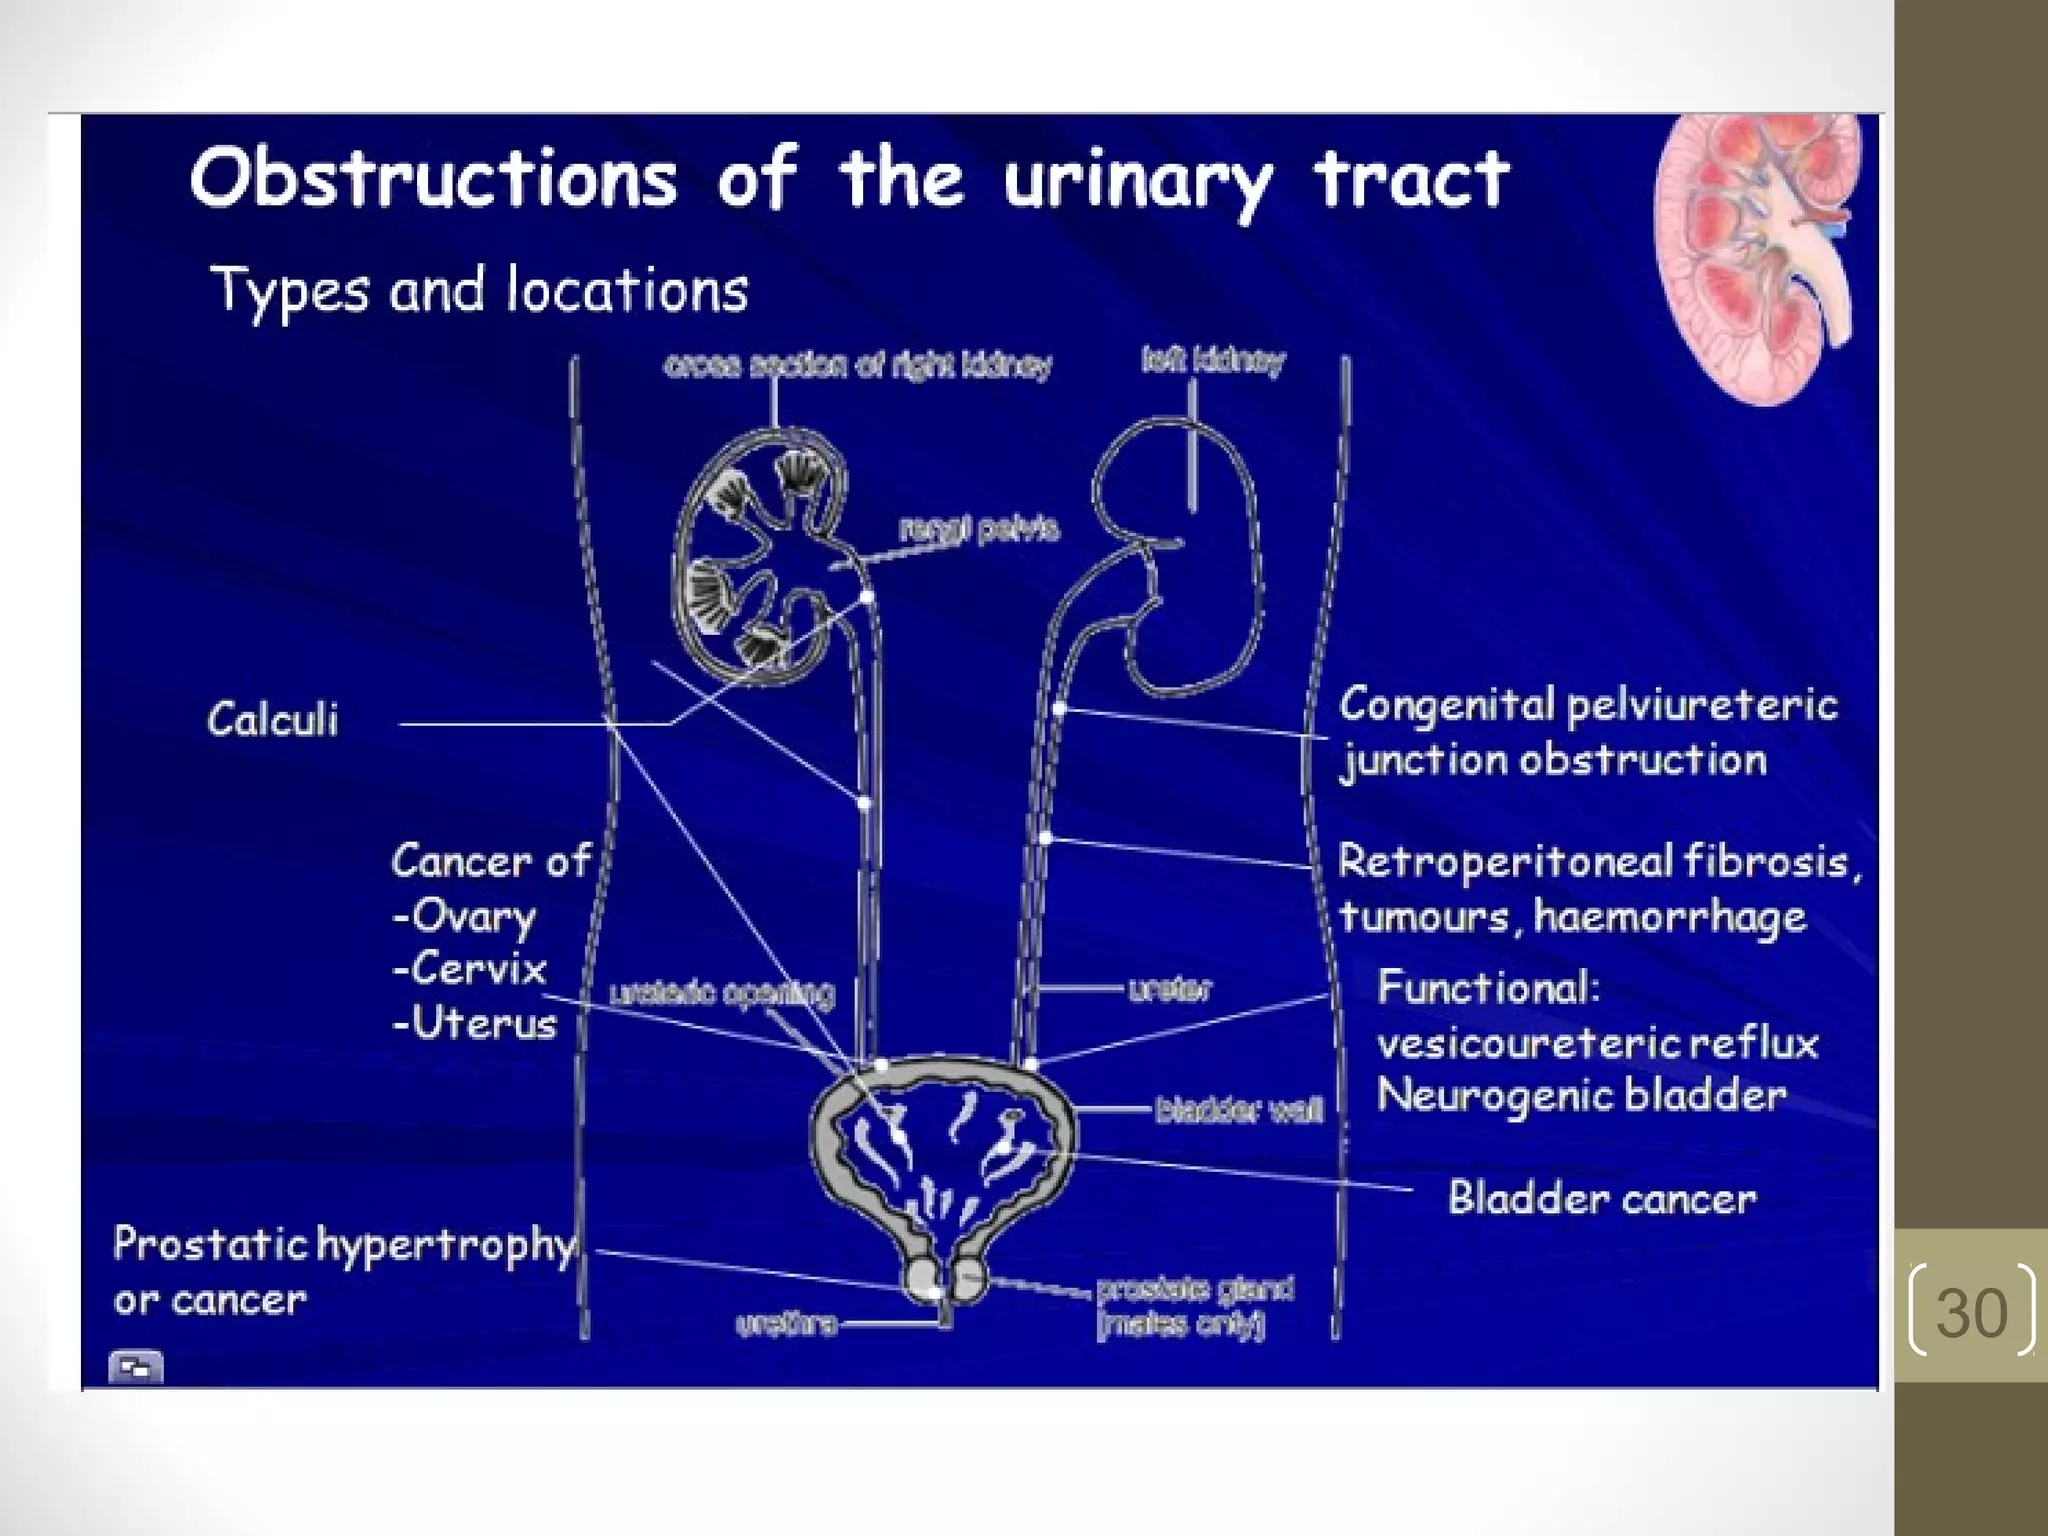

Hydronephrosis is the dilation of the renal pelvis and calyces caused by obstruction of urine flow from the kidney. It can be caused by issues in the ureter, bladder, or urethra that limit urine outflow. Unilateral hydronephrosis may cause dull flank pain while bilateral obstruction can lead to decreased urine output. Left untreated, hydronephrosis can damage kidney tissue and impair renal function. Diagnosis is made through imaging tests like intravenous pyelogram. Treatment focuses on resolving the underlying cause of obstruction.